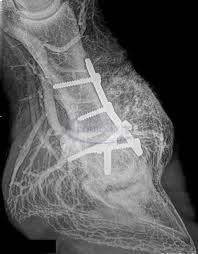

La radiologia convenzionale è l’esame di primo livello per lo studio di molteplici distretti corporei e in particolare dell'apparato respiratorio e scheletrico (cranio, colonna vertebrale, segmenti ossei). Questa metodologia fornisce importanti indicazioni di base su molte patologie, sia traumatiche che degenerative e artrosiche nonché malformative. La radiologia convenzionale si risulta anche di grande efficacia per individuare patologie o problematiche all'apparato urinario e all'addome, da approfondire successivamente con esami diagnostici più accurati e precisi.